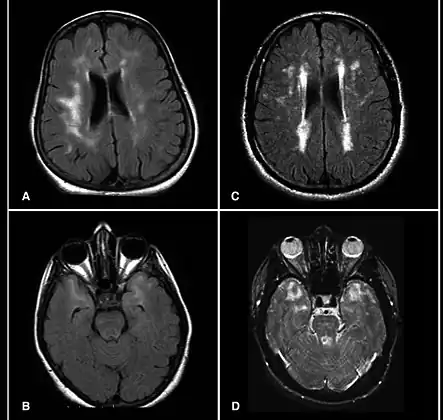

| Brain MRI from patients with CADASIL showing multiple lesions. | |

MRIs show hypointensities on T1-weighted images and hyperintensities on T2-weighted images, usually multiple confluent white matter lesions of various sizes, are characteristic. These lesions are concentrated around the basal ganglia, peri-ventricular white matter, and the pons, and are similar to those seen in Binswanger disease.[2][11] These white matter lesions are also seen in asymptomatic individuals with the mutated gene.[12] While MRI is not used to diagnose CADASIL, it can show the progression of white matter changes even decades before onset of symptoms.